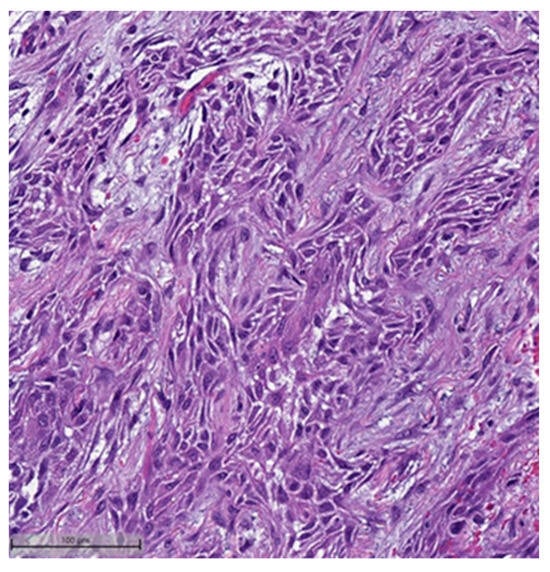

This system is primarily based on the specific metaplastic elements present within the tumors, while also highlighting the potential overlap that can exist between various histological subtypes [6]. Consequently, numerous cases diagnosed as MpBCs, are accompanied by a detailed description of the histological component or a combination of different component types and/or differentiations. The following figures illustrates a few examples: spindle cell carcinoma component with pleomorphic features (Figure 4), metaplastic breast carcinoma with chondroid differentiation (Figure 5), metaplastic breast carcinoma with a matrix-producing component (Figure 6), metaplastic breast carcinoma with osseous differentiation (Figure 7), and extensive trabeculae bone and hematopoietic tissue (Figure 8).

Figure 6.

Metaplastic breast carcinoma with matrix-producing component (H&E, 20×).